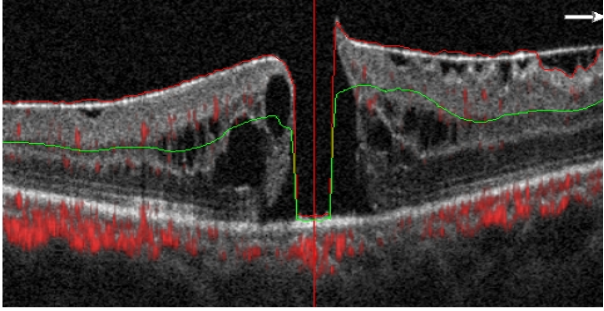

圖2 特發(fā)性黃斑裂孔OCT圖